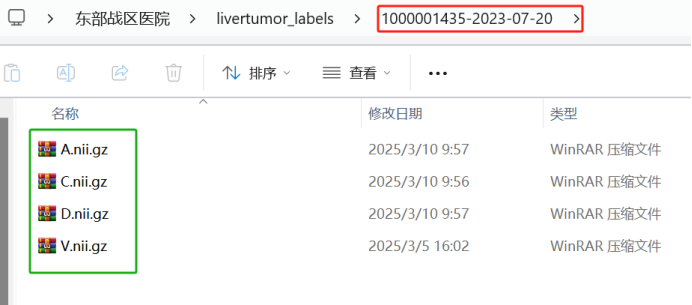

于每个标注病例,里面的内容包括四个期的肿瘤标注文件,每个文件的命名必须和原始图像的命名保持一致。比如原始图像/images/1000001435-2023-07-20文件夹下A.nii.gz文件对应的标注路径应该在/livertumor_labels/1000001435-2023-07-20/A.nii.gz